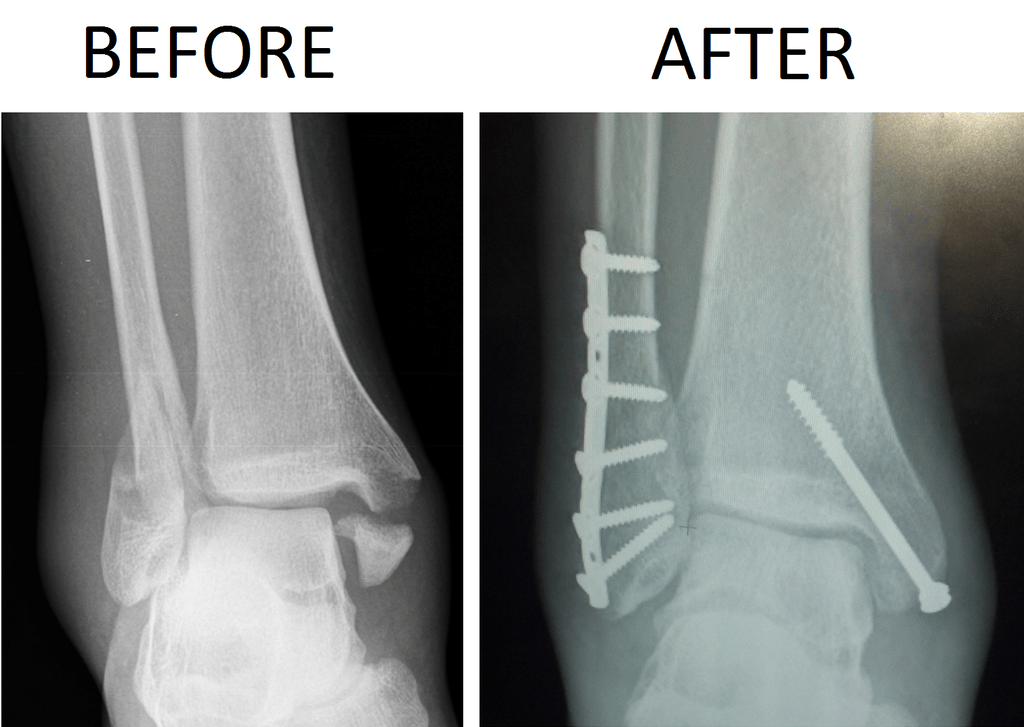

This type of fracture can occur when both malleoli are fractured. 2 words

Bimalleolar Fracture